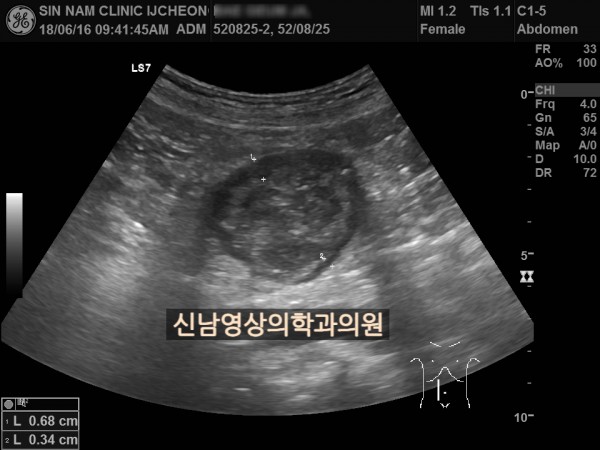

본 환자분은 변비가 지속되면서 좌하복부 통증이 있으셨던 분으로 본원에서 복부 초음파 검사를 진행하였습니다.

하행 결장 부위에서 장이 두꺼워진 소견이 보여 진행된 대장암의 가능성이 농후해보여 대학병원으로 전원해 대장내시경을 받고, 수술로 2기암으로 진단되신 케이스입니다.

위암이나 대장암은 점막에서 발생하는 0기암은 초음파로 진단할 수 없지만 대장암이 점막을 넘어 근육층이나 장간막으로 퍼지게 되면 초음파 검사상 근육, 장간막 부위가 두꺼워지는 소견으로 나타나 발견하기도 합니다.